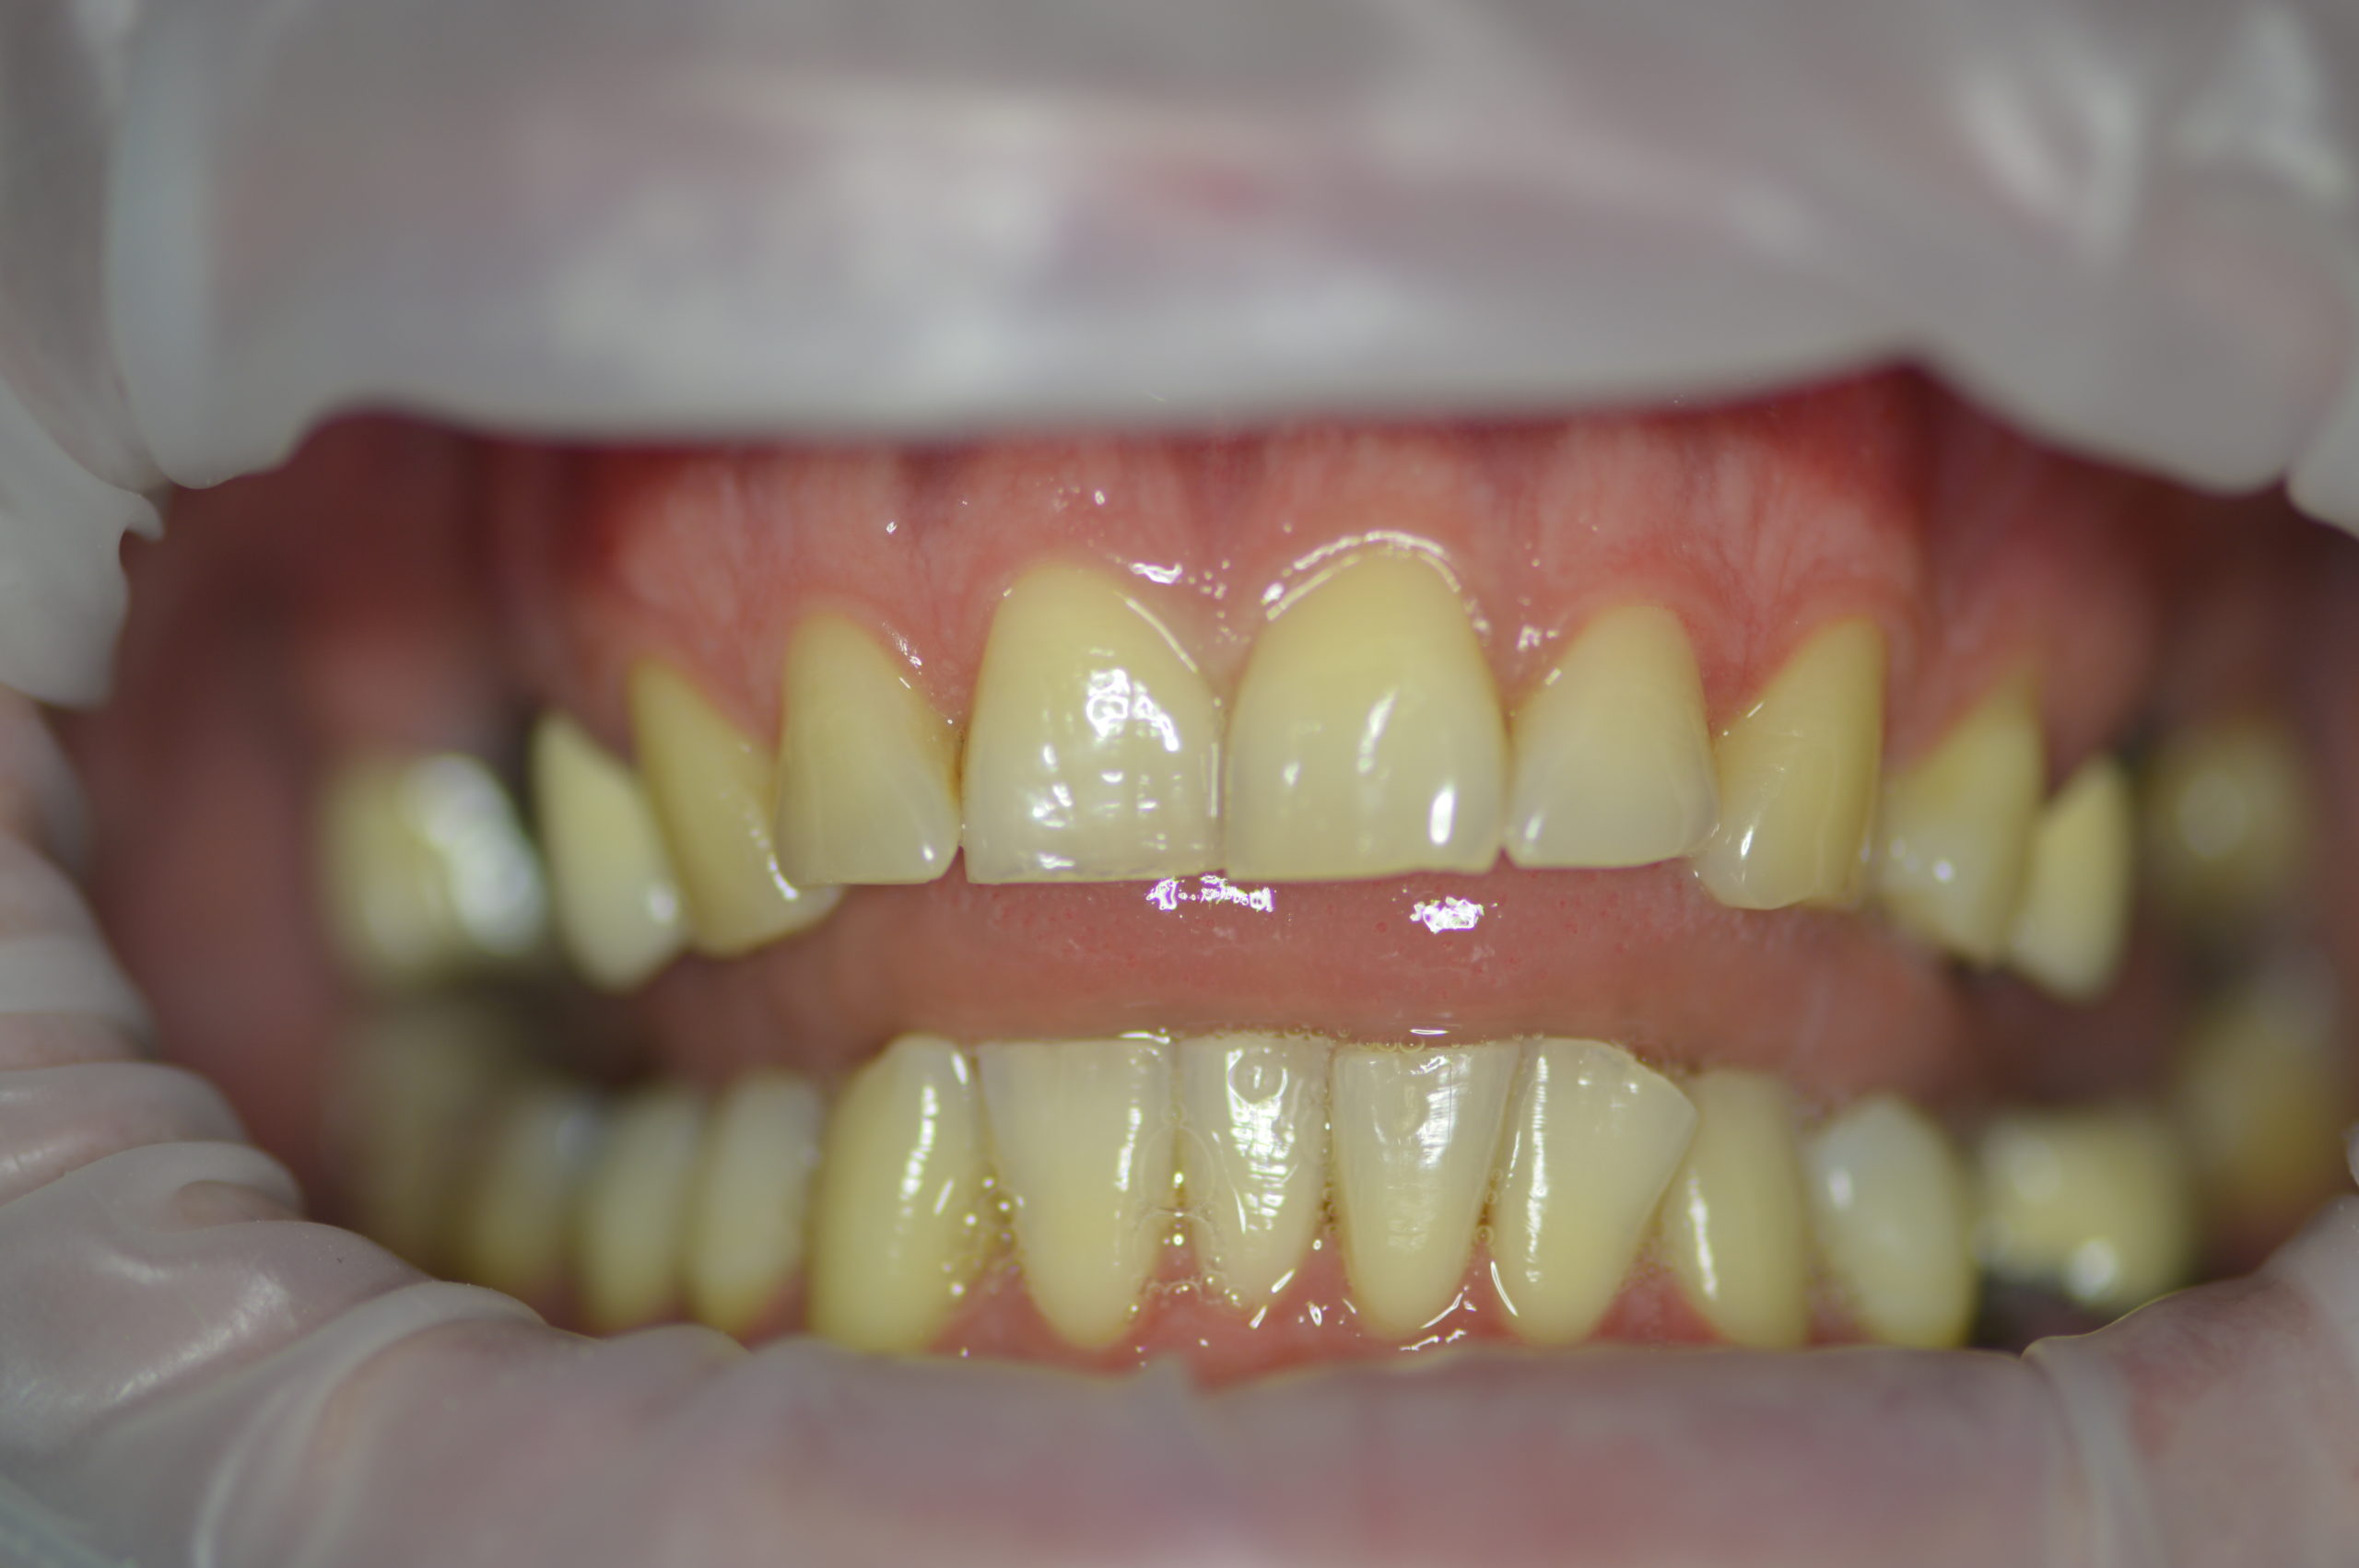

Photo BEFORE treatment with dental implants and dental crowns

Mr. Peter’s (32 years old) wish was to have nice and bright smile. Dr. Martin has made a treatment plan that contained 6 dental implants (4 for upper jaw and 2 for lower jaw), one tooth extraction, 5 re-root canal treatments and 12 dental crowns. After patient left examination room our staff discussed every detail of treatment with him and Mr. Peter made a booking for implant appointment with Dr.Martin in just 2 weeks after consultation.

The surgery began with the extraction of tooth number 26 and bone graft on upper jaw and it continued with implantation on 27, 26, 16 and 15 on upper jaw and 35 and 37 on lower jaw.

3,5 month after implantation Mr. Peter returned to our dental clinic to continue his treatment with four re-root canal procedures. Doctor decided to gave the implants more time for healing so patient returned in 2 months to get his front natural teeth reshaped and get impressions for his future implant crowns and zirconium dental crowns.